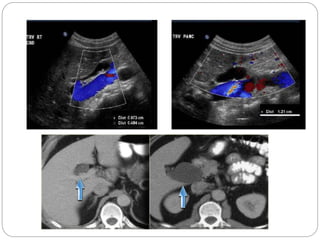

Parapelvic cyst

Severe hydronephrosis with

proximal hydro ureter

Moderate hydronephrosis on

right and severe on left